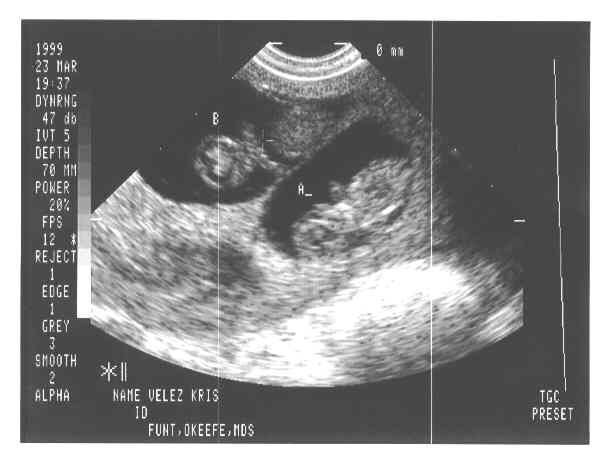

V-Twins

eggs2.JPG - 19.8 K eggs3.JPG - 22.4 K eggs4.JPG - 11.7 K babies-1a.JPG - 21.3 K